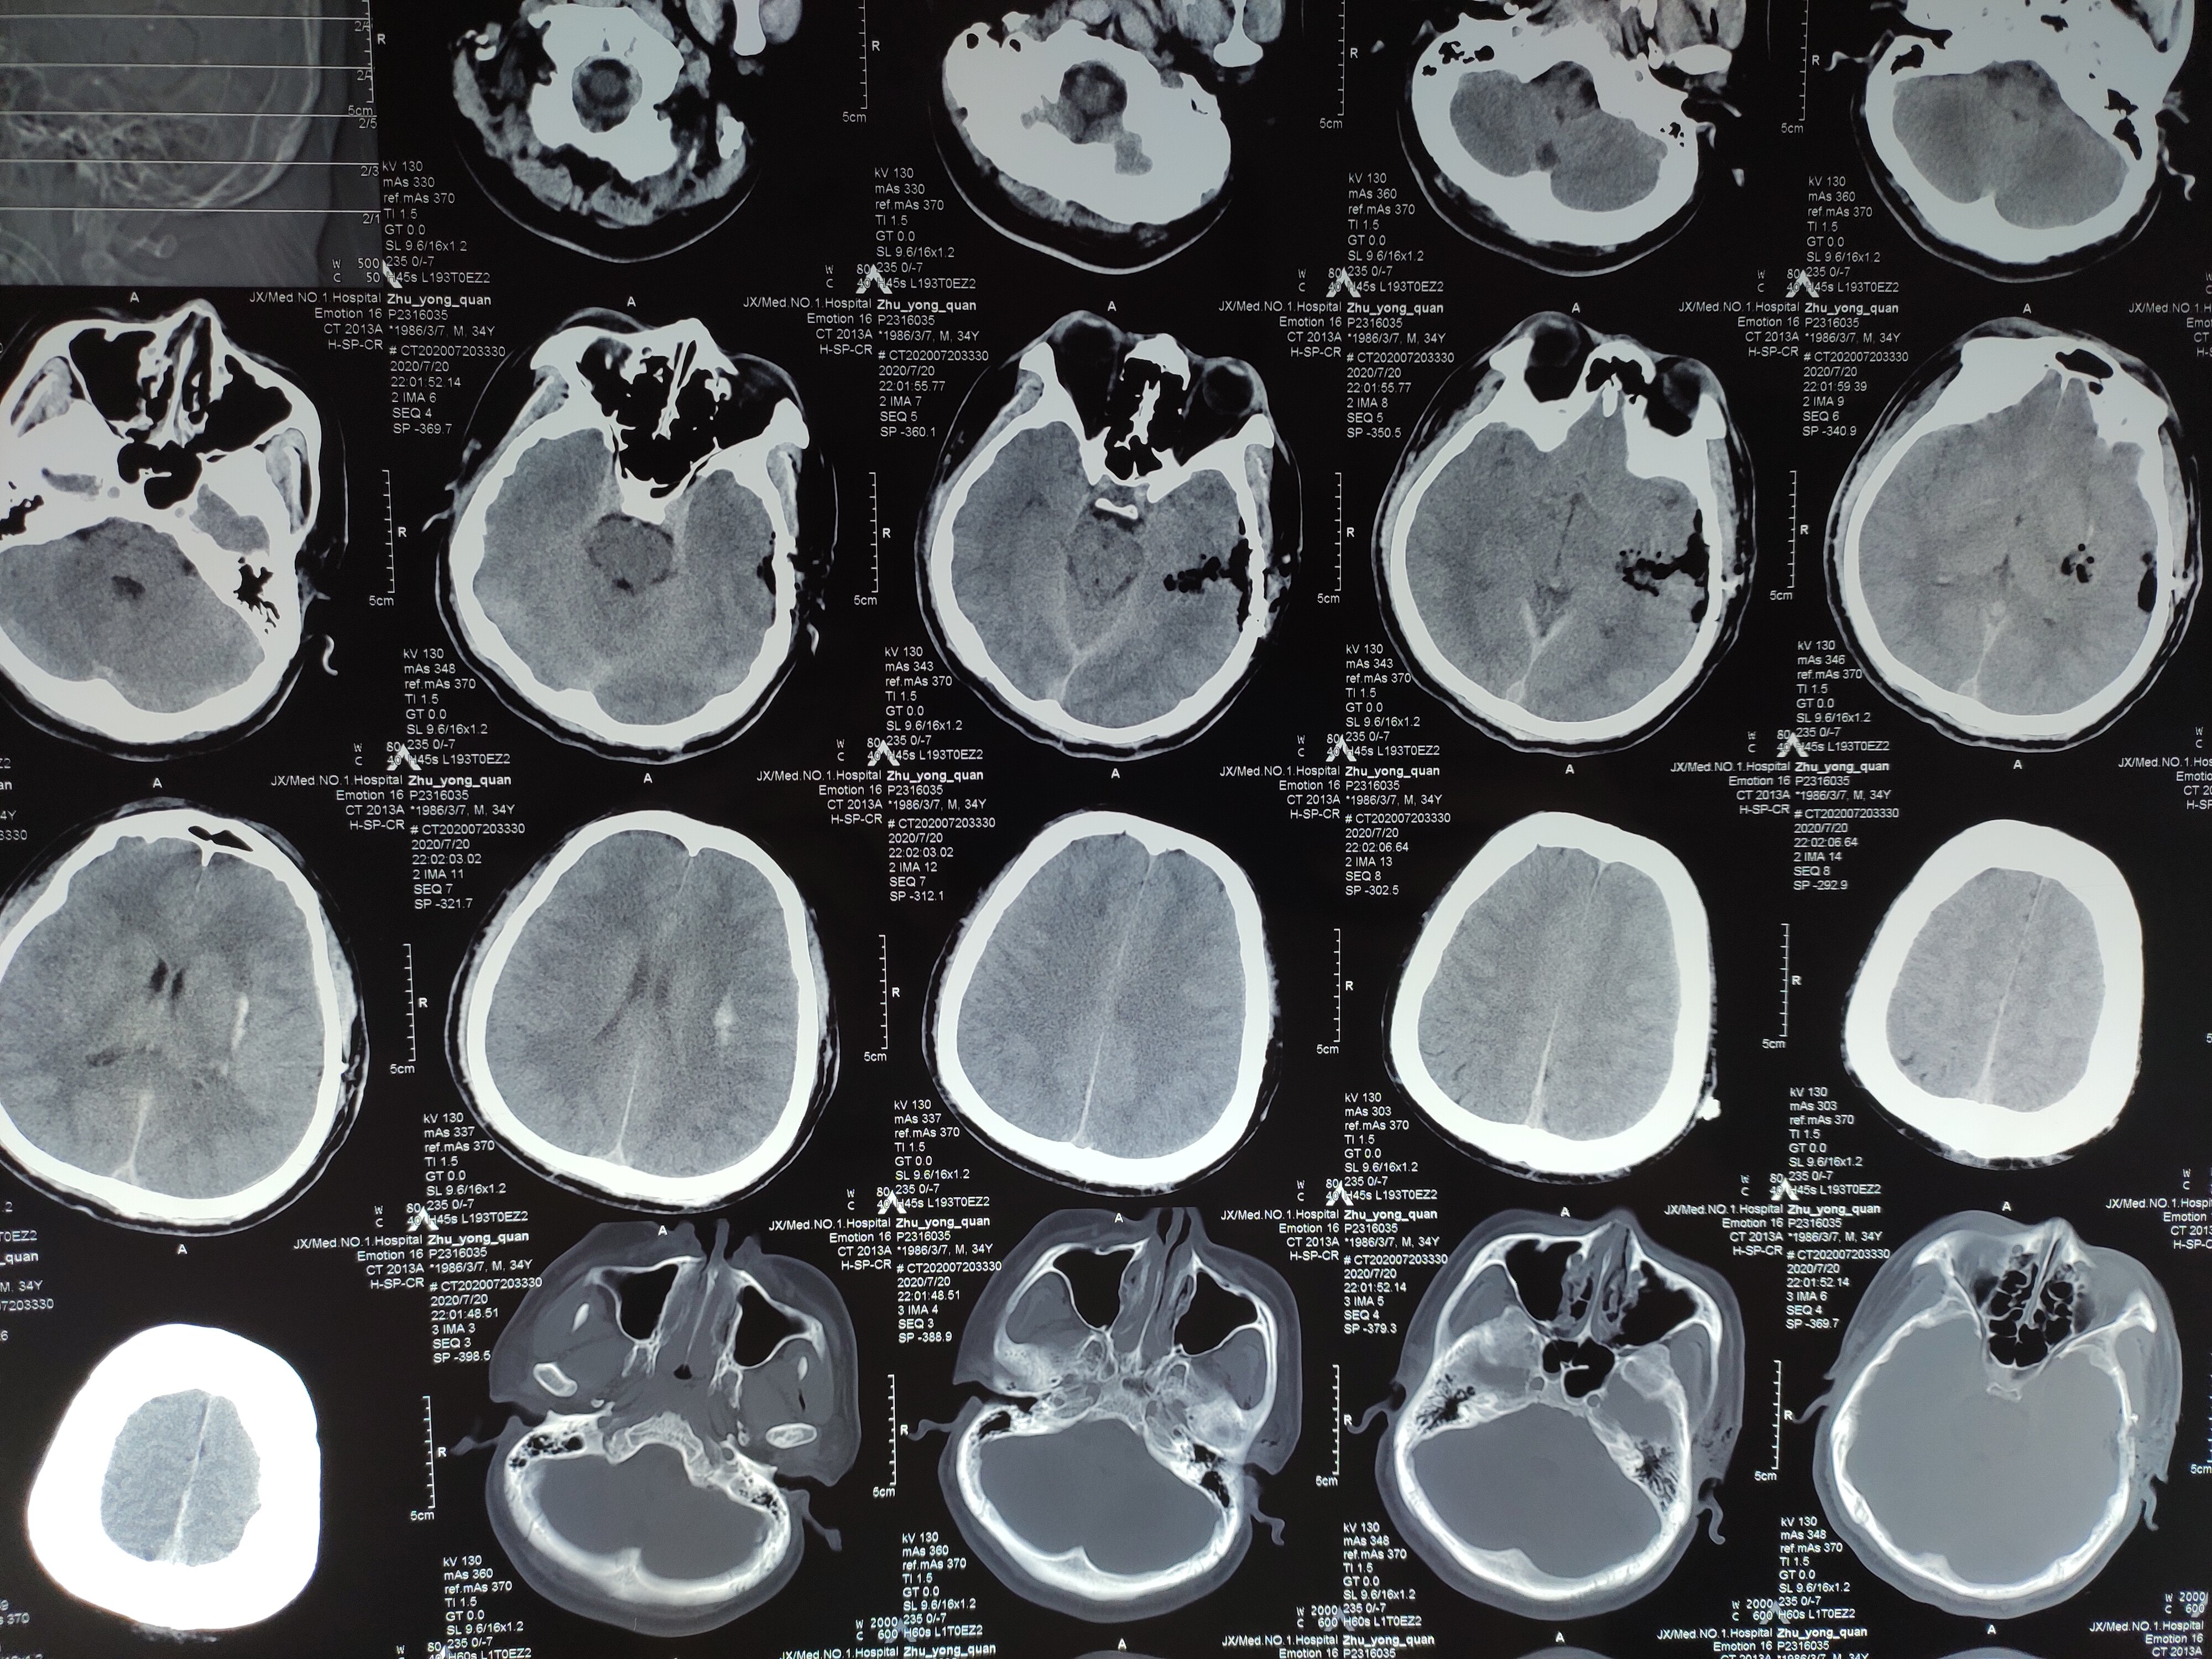

基底节出血1例

图片尺寸3264x2448

左侧基底节脑出血伴高血压1例

图片尺寸2448x3264